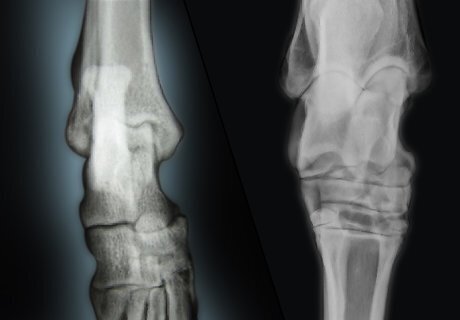

Let the vet take an X-ray of your dog’s affected leg. The vet may then sedate or anesthetize your Rottweiler so she can take X-rays of your dog’s hock and any other areas that may be sore. Usually, two views are taken of your dog’s hock in the X-rays. One view is taken from front to back (anterior-posterior) and one view is taken side to side (lateral). Doing two views in the x-rays will help the vet rule out other conditions such as a fracture, an infection, and cancer. However, X-rays are not a foolproof way to detect OCD in your dog’s hock. In the early stages of the condition, the only clear evidence of OCD is a flap of cartilage on your dog’s hock or a chip off the cartilage. It may be difficult to spot these small issues on an X-ray.